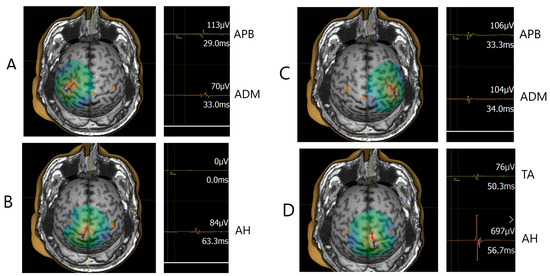

2.4. Navigated Transcranial Magnetic Stimulation (TMS) Procedure